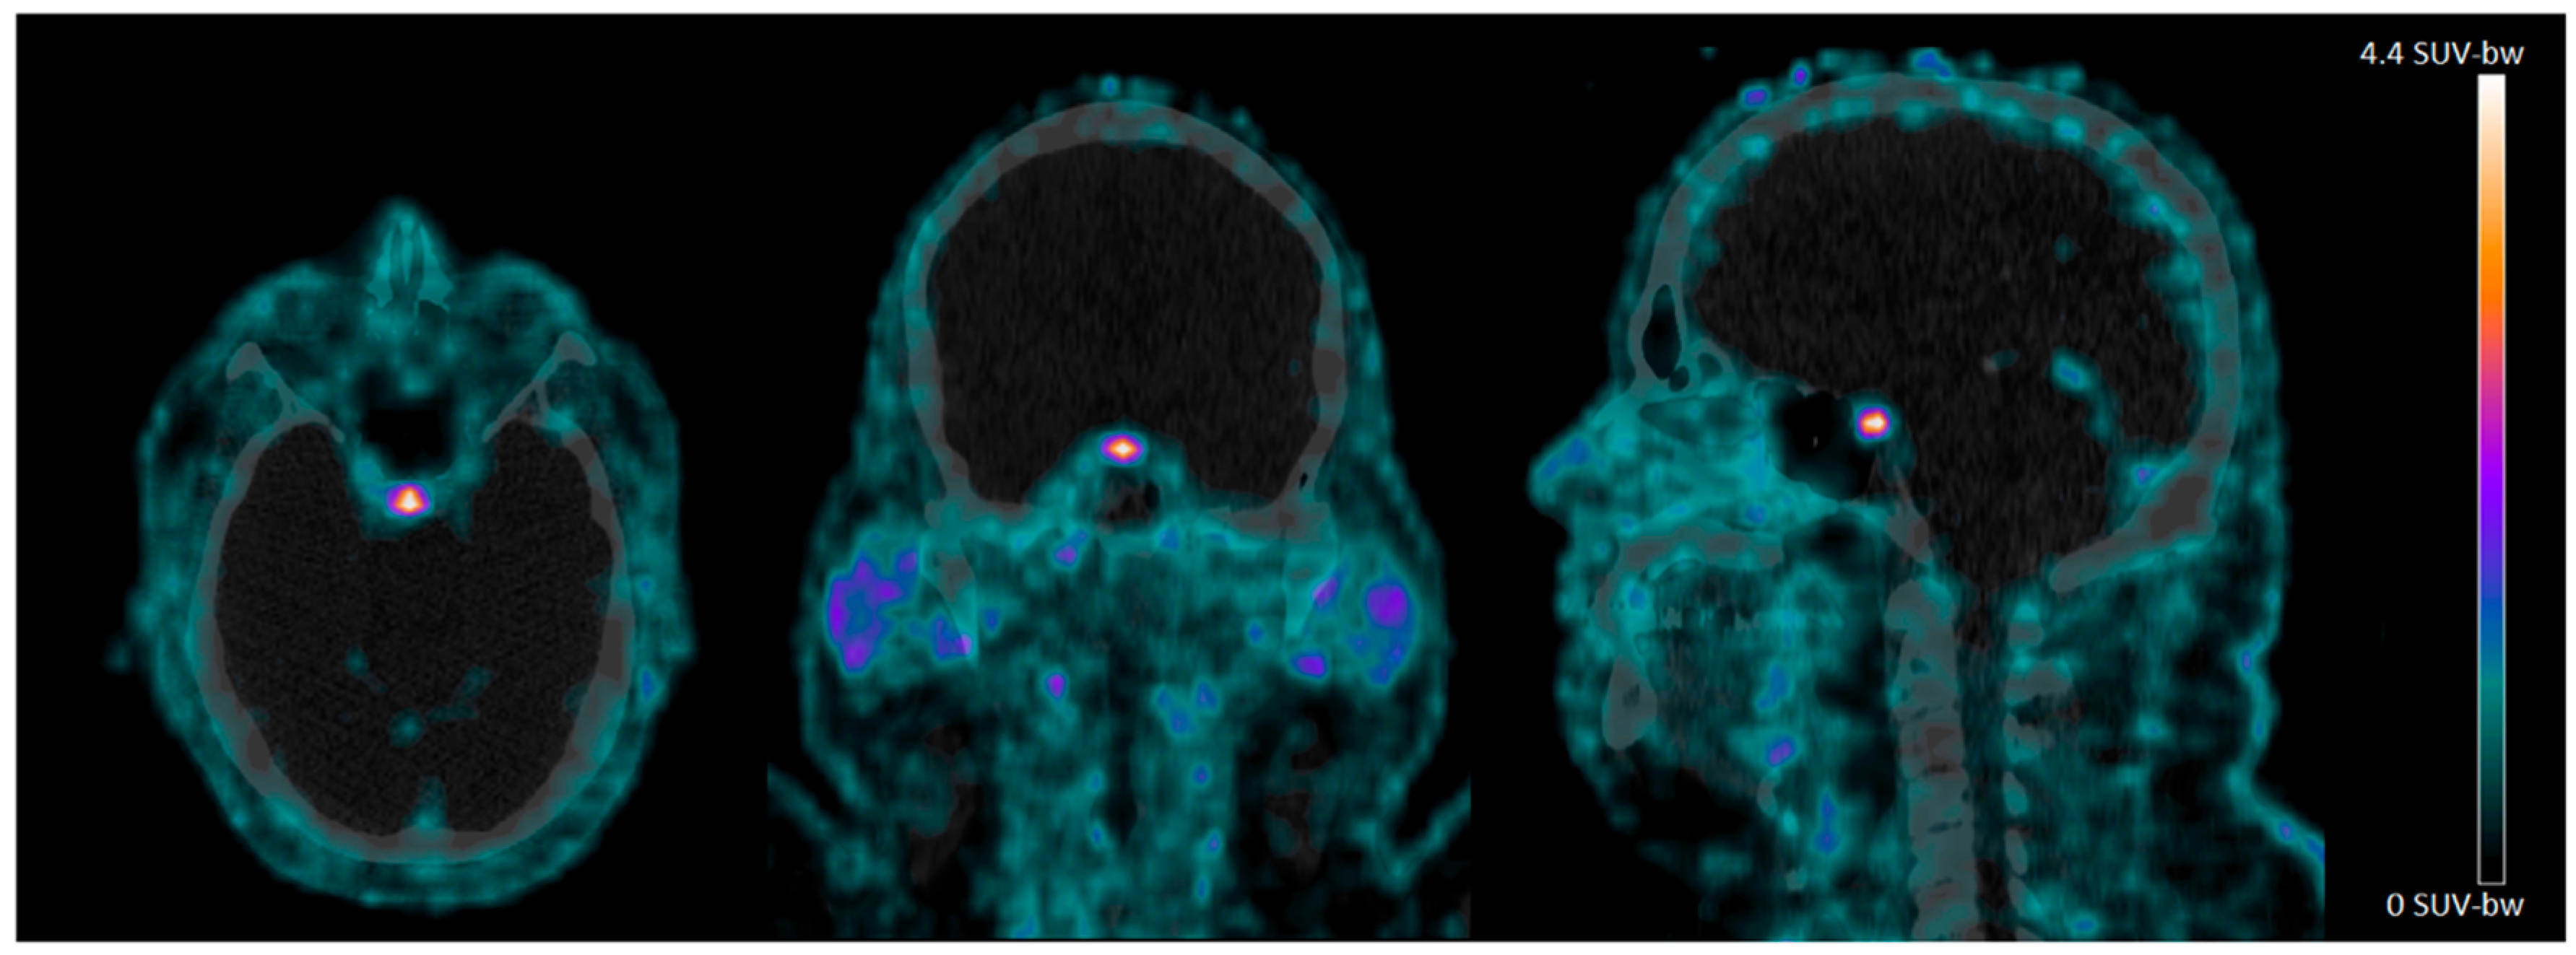

In the CNS, we observed clear 68Ga-NODAGA-exendin-4 uptake in the pituitary area (Figure 1), which was variable between subjects, with a mean SUVmean of 1.7 ± 0.57 (range: 0.88–2.7) and mean SUVmax of 4.3 ± 3.3 (range: 1.4–9.1). However, no 68Ga-NODAGA-exendin-4 uptake was visible in other parts of the brain (mean SUVmean: 0.0010 ± 0.0066 (range: 0.0001–0.21) and SUVmax of 0.17 ± 0.095 (range: 0.013–0.32)) (Table 2).

In this study, we show that there is no significant uptake of 68Ga-NODAGA-exendin-4 in the brain (parts inside the blood–brain barrier; BBB) of subjects with obesity, although there is clear uptake in the pituitary. We also reproduce the accumulation of 68Ga-NODAGA-exendin-4 PET in the pancreas [31].

4.2. 68Ga-NODAGA-Exendin-4 Uptake in the Pituitary Area

We can show significant 68Ga-NODAGA-exendin-4 uptake in the pituitary of subjects with obesity. Since earlier studies showed the ability of 68Ga-NODAGA-exendin-4 PET to visualize GLP-1 receptors in beta-cells of the pancreas [31], and the pituitary is located outside the blood–brain barrier (BBB) and expresses GLP-1 receptors extensively in rats and humans, particularly in the neuro-pituitary [35,36], this was an expected finding. As GLP-1 receptors play an important role in appetite and stress regulation, and the pituitary is an essential part of the hypothalamus–pituitary–adrenal gland (HPA)-axis, the GLP-1 receptor expression in the pituitary may play a role in appetite and stress regulation in humans [37,38,39]. Importantly, GLP-1 receptor tracers such as 68Ga-NODAGA-exendin-4 offer the unique opportunity to test this postulate directly in humans.

In the present study, we were not able to differentiate binding to the pituitary from binding in the basal hypothalamus. Therefore, we cannot exclude that we did not measure only uptake in the pituitary, but also in the basal hypothalamus. In other ongoing studies, by also acquiring magnetic resonance (MR) images for better anatomical referencing, we aim to evaluate this relevant topic.

Figure 1. 68Ga-NODAGA-exendin-4 PET/CT scans of the head acquired 60 min after injection in an obese subject. Note the intense uptake in the pituitary.